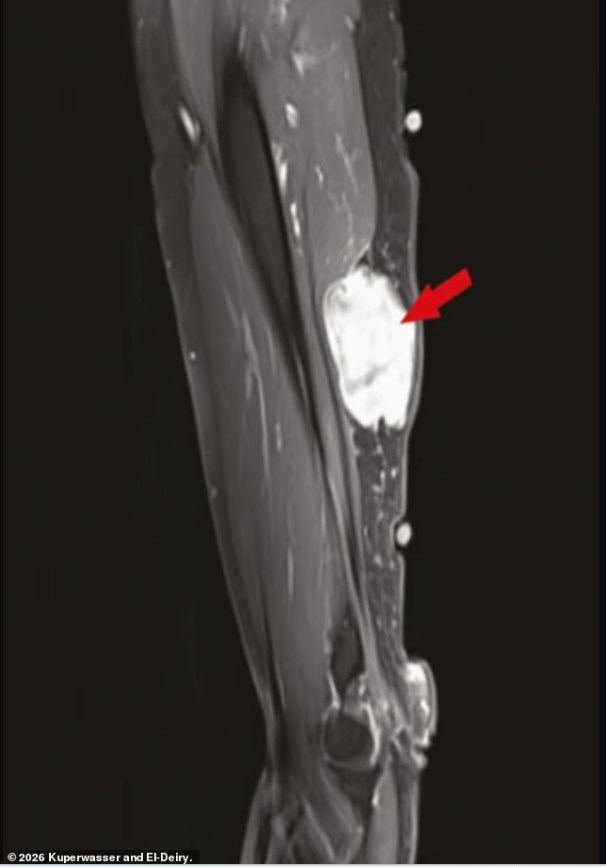

Në këtë rishikim, autorët analizuan 69 studime dhe raporte rastesh të publikuara më parë në mbarë botën, duke identifikuar 333 raste ku kanceri ishte diagnostikuar rishtazi ose ishte përkeqësuar me shpejtësi brenda pak javësh pas vaksinimit kundër Covid-19.

Autorët vunë re gjithashtu raste të përkeqësimit të papritur të kancereve me rritje të ngadaltë, që më parë kishin qenë të qëndrueshme, si dhe raste ku vaksina dukej se kishte “aktivizuar” viruse të caktuara të lidhura me kancerin, si herpesvirusi njerëzor 8.